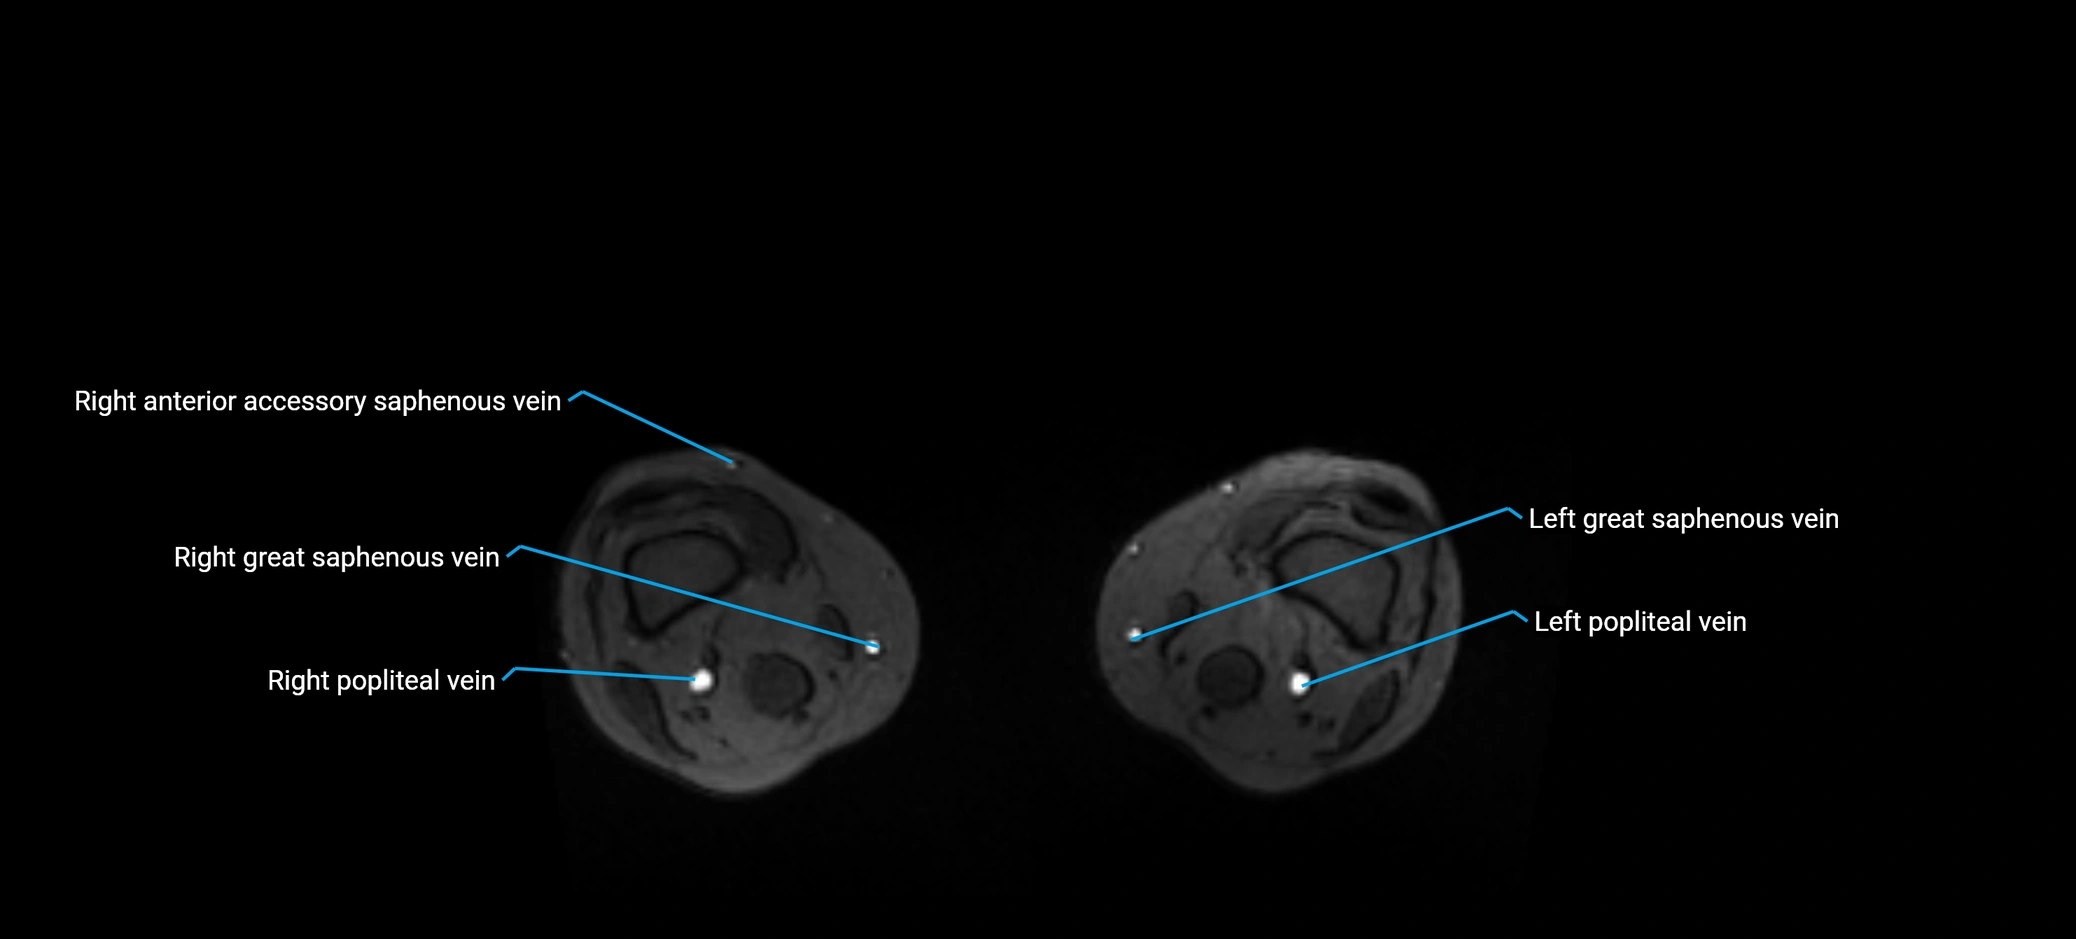

MRI image

image